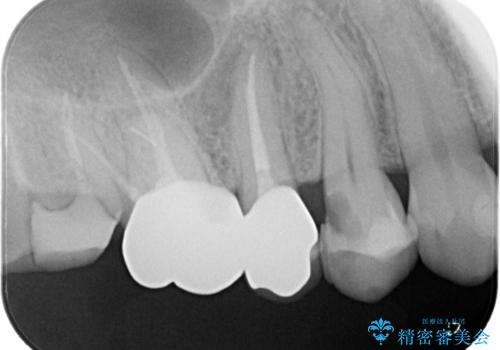

右上4番に歯冠色インレーが入っており、遠心側室エリアのマージン不適を認め、そこに汚れが溜まりやすい状態となっていました。

現在入っているインレー・CR裏層を除去し、再度CR裏層・セラミックインレー形成しました。